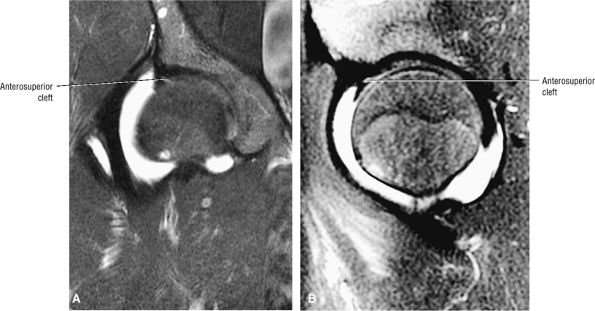

An anterosuperior cleft (Fig. 3.61) may be seen as a normal variant in the presence of a normal lateral acetabular labrum. On anterior coronal or sagittal images, this cleft is seen as a partial undercutting of the labrum on a single image. The extension of fluid into this cleft occurs from the femoral side. It may be more commonly seen in labral hypertrophy associated with mild developmental dysplasia of the hip (DDH).

FIGURE 3.61 ● Coronal (A) and sagittal (B) FS PD FSE images of an anterosuperior cleft in a patient with mild DDH and a hypertrophied labrum. The cleft does not extend completely through the lateral or anterior labrum.